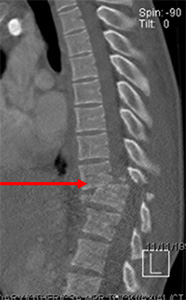

Gentleman after a motor vehicle accident comes into the hospital unable to move his legs. A CT shows a fracture dislocation (arrow). Emergent surgery is done to help realign the fracture as best as possible.